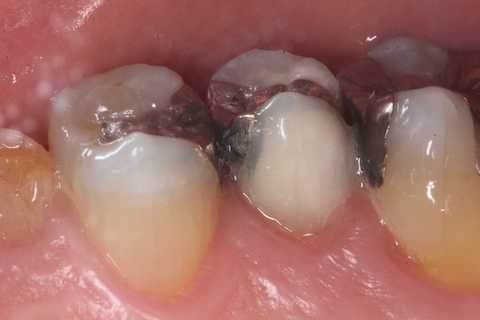

今日の充填治療56(メタルインレー脱離) 2025.01.04